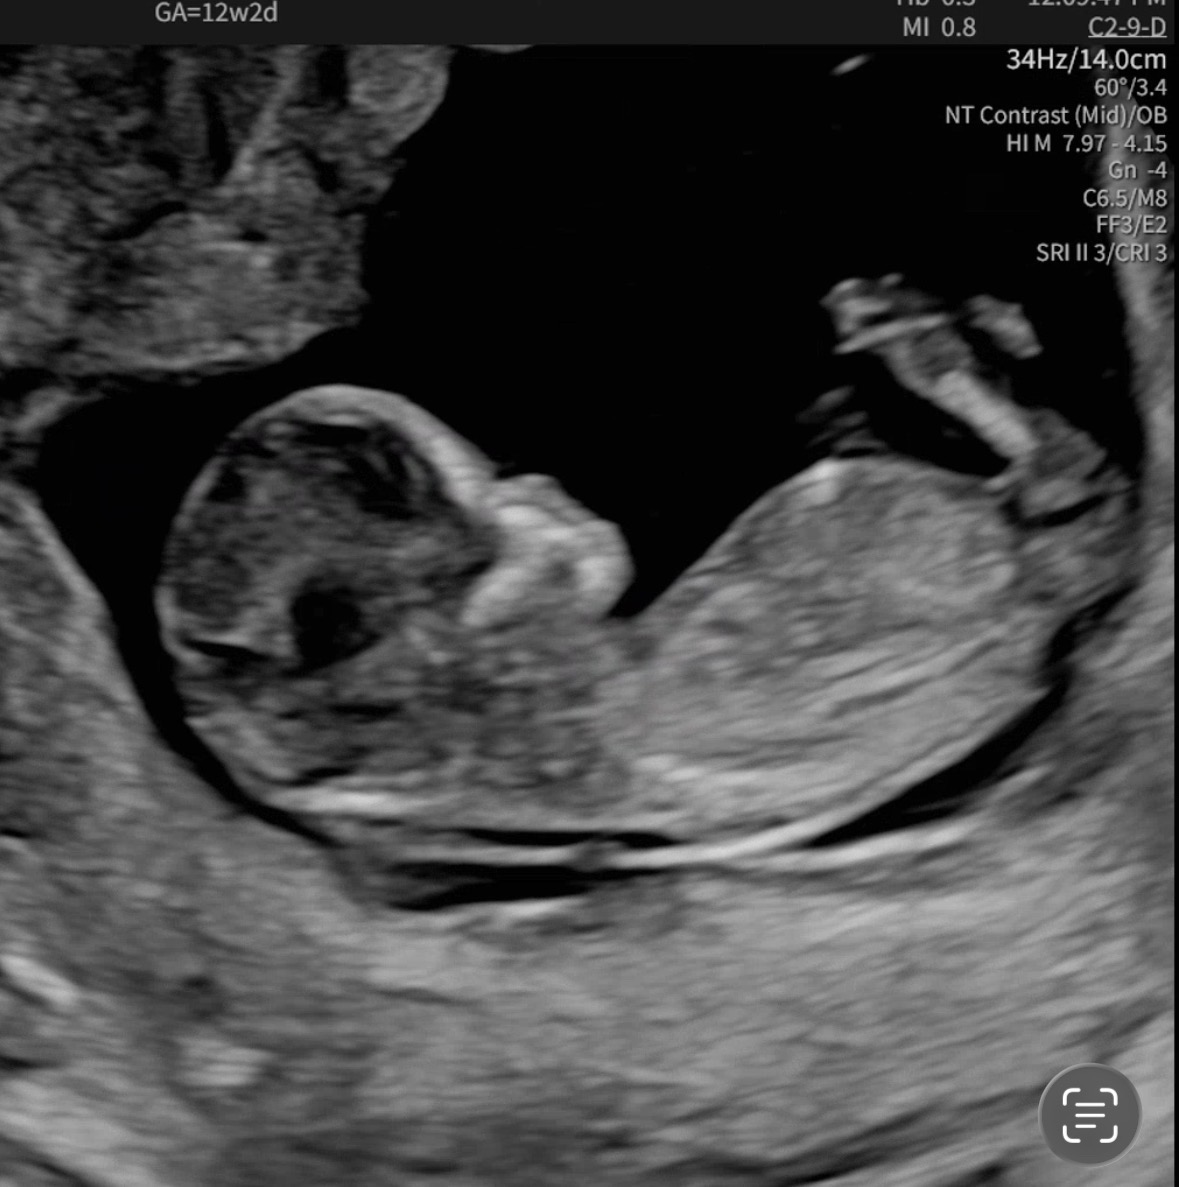

12주 2일차 각도법 궁금해요

12주 2일차, 아기 성별이 궁금해요 한번씩 투표해주시면 감사합니다💕